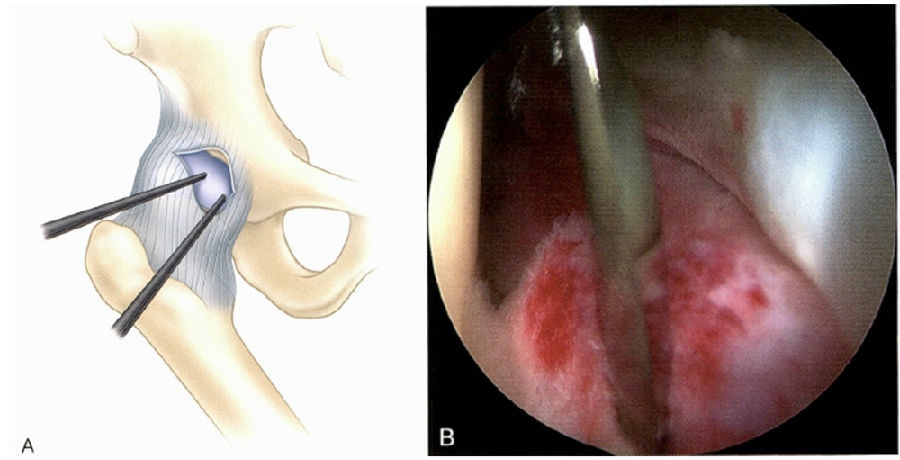

通过套管置入关节镜切割刀,轻微的横向切开关节囊,以增加手术器械的操作空间(图51-72A和B)。

图51-72 关节囊切开。A.前外侧和前方入路;B.自前方入路观察